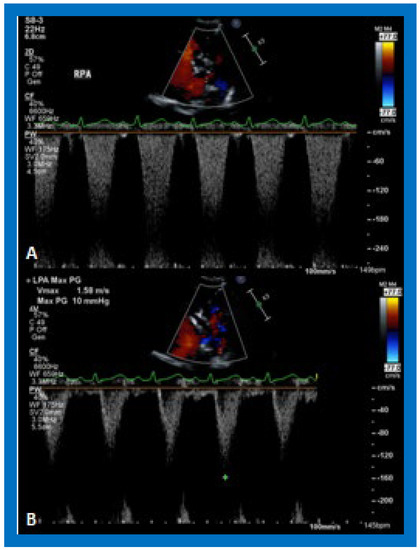

Figure 21. Selected video frames demonstrating flow acceleration across the right (RPA) (A) and left (LPA) (B) pulmonary arteries in a patient with a Blalock–Taussig shunt. These slightly higher than normal velocities do not indicate stenosis of the branch pulmonary arteries.

In patients who had an aorto–pulmonary shunt (most commonly modified Blalock–Taussig), the shunt may be visualized by color flow imaging (Figure 19), although it is difficult to image it only by 2D. High Doppler flow velocities across the shunt are normally recorded (Figure 20), and they reflect the systolic pressure difference between the aorta and PAs. Low Doppler flow velocities across the shunt, however, may indicate high PA pressures. The flow into branch PAs can easily be demonstrated by color flow Doppler imaging (Figure 19B). Flow acceleration in the branch PAs is usually seen (Figure 21) and is of no concern. However, high flow velocities may indicate branch PA stenosis.